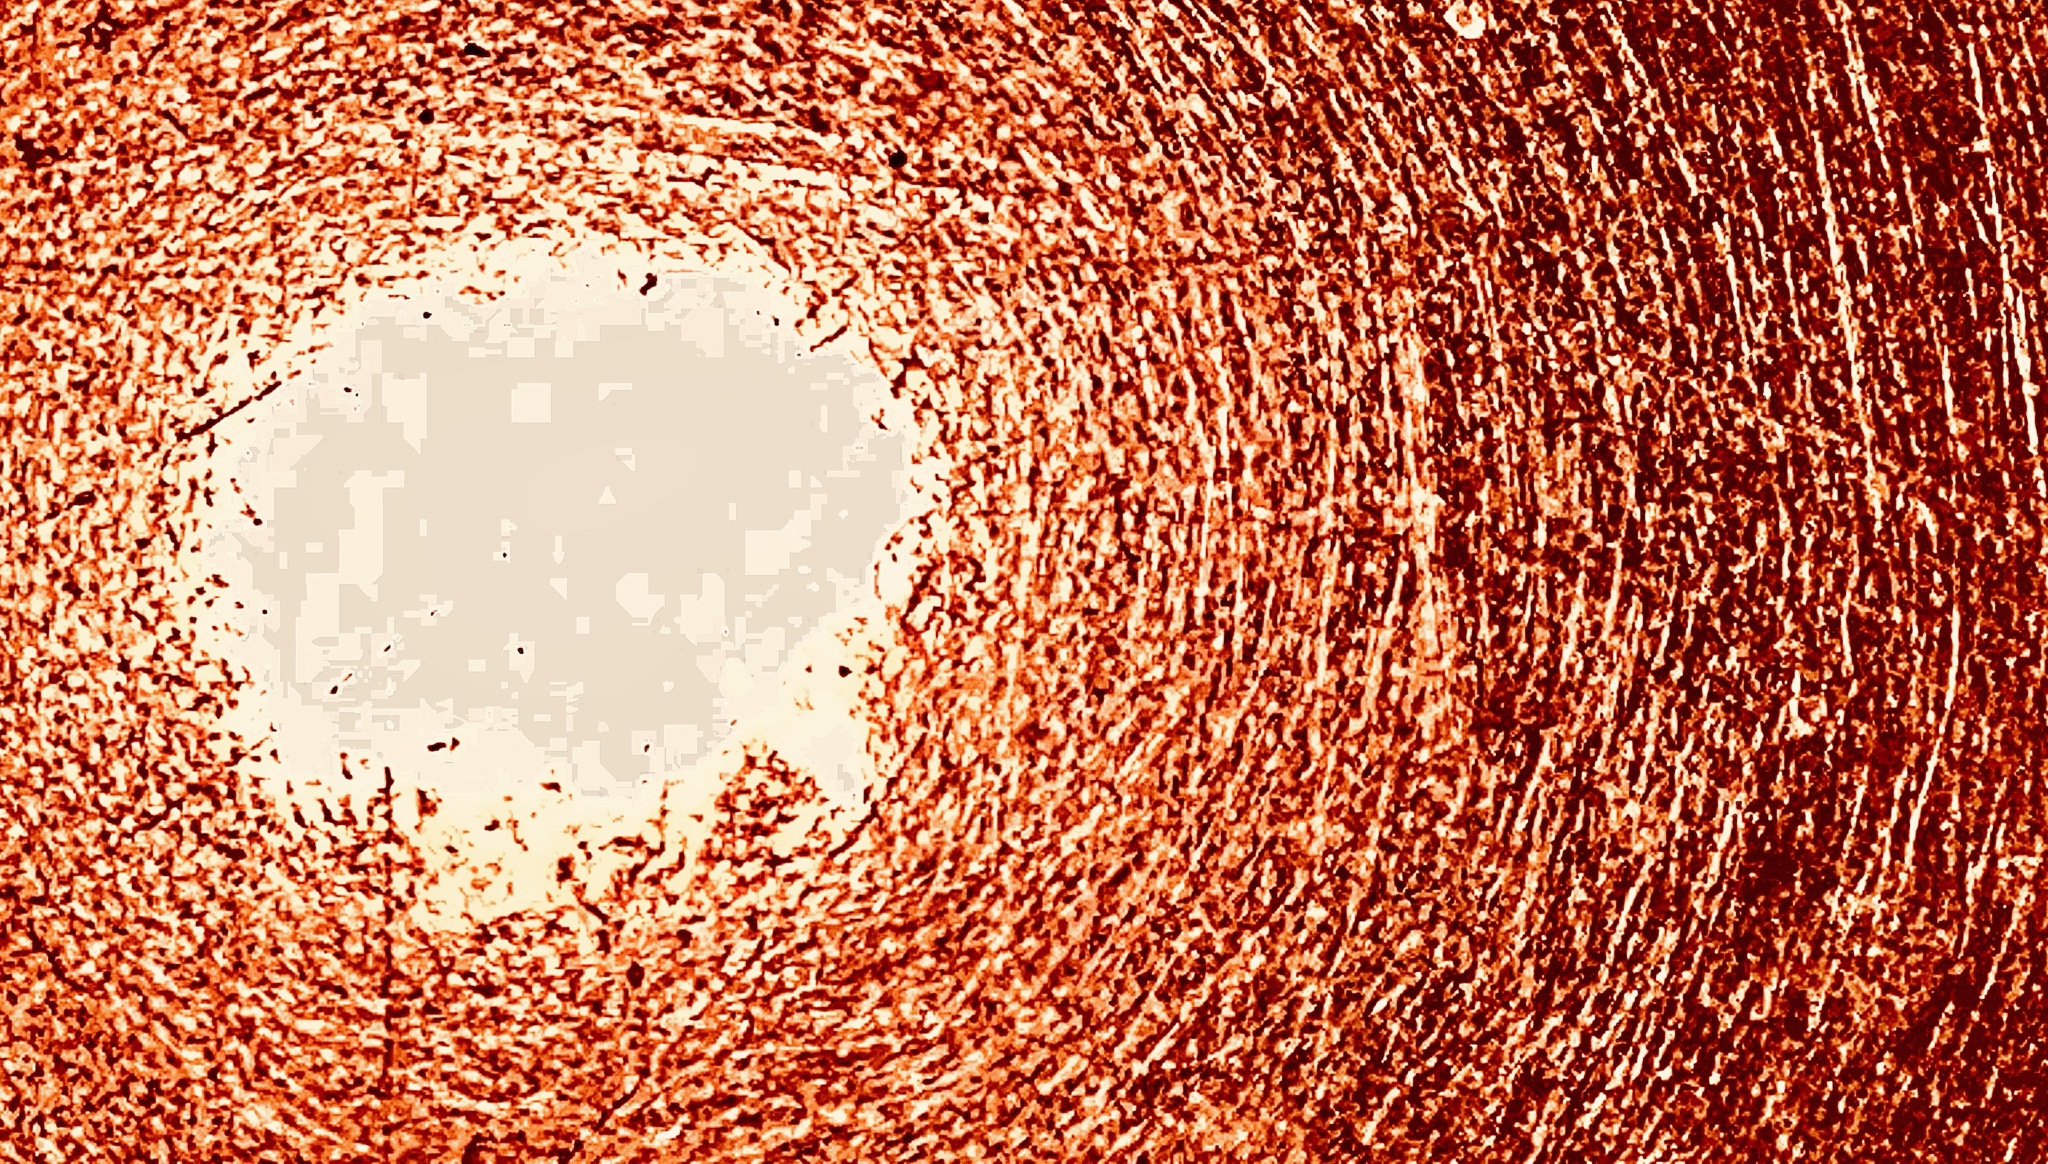

Silver Halide Crystals (Haiku)

Yellow filaments

Bind circles of confusion

To silver halide